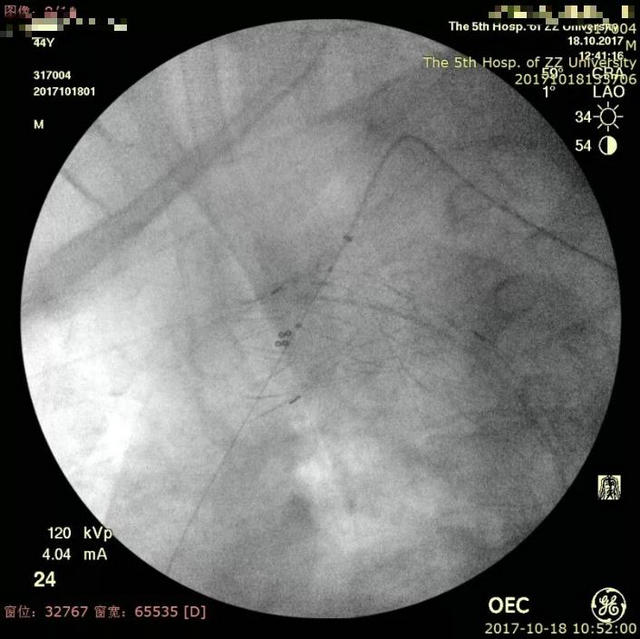

近日,郑州大学五附院血管外科就成功为一位累及左锁骨下动脉的病人开展了这项技术,取得了很好的效果。这是一位44岁的中年男性,突发腰背部疼痛,曾在当地按泌尿系结石进行体外碎石治疗,治疗后疼痛仍不缓解,再查CTA提示主动脉夹层,随即急诊转入进一步治疗。主动脉CTA显示Stanford B型夹层,但夹层累及左锁骨下动脉,如果不封堵该动脉则存在夹层继续进展的较大可能,而封堵了该动脉则可能导致头颅和左上肢的缺血症状,而且患者年轻,保留左锁骨下动脉的必要性大。经过科室的充分术前讨论,最后决定对该患者行“胸主动脉夹层覆膜支架腔内隔绝术,左锁骨下动脉原位激光开窗并支架置入术”,手术由王兵教授和崔文军副主任医师亲自操刀,手术成功,按原定计划顺利完成,用时不到2小时。术后患者恢复良好,腰背部疼痛消失,左上肢血供良好,肱动脉、桡动脉搏动有力,无头晕等不适发生,复查主动脉CTA提示支架位置、形态良好,夹层隔绝良好,左锁骨下动脉支架通畅,近期即将顺利出院。

▲ 原位激光开窗